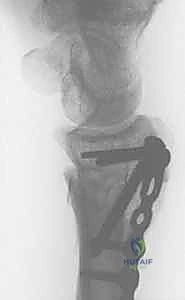

5. التثبيت بصفائح التيتانيوم (Internal Fixation)

للحفاظ على الوضع الجديد والمثالي للعظم، يتم استخدام صفائح تيتانيوم متقدمة ذاتية الغلق (Volar Locking Plates). هذه الصفائح مصممة تشريحياً لتلائم شكل الكعبرة، وتوفر تثبيتاً قوياً جداً يسمح للمريض ببدء تحريك أصابعه في اليوم التالي للعملية.